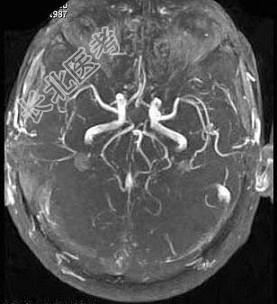

- 单项选择题男,35岁, 头痛半年加重1周,左侧肢体无力, 影像检查如图所示,最可能的诊断为

A、脑血管畸形

B、脑梗死

C、脑出血

D、脑炎

E、脑静脉性血栓